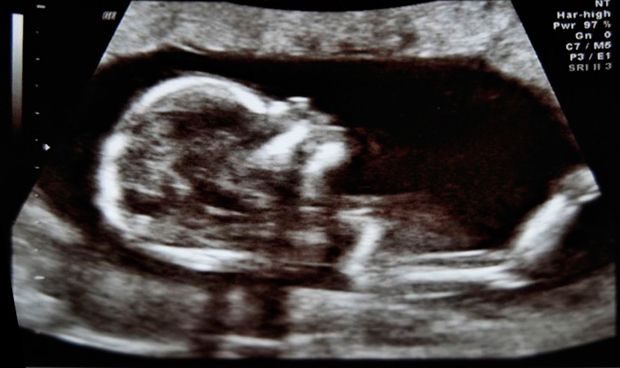

El líquido uterino podría desempeñar un papel más allá del conocido. Hasta el momento, se sabía que era el encargado de crear el ambiente propicio para la migración de los espermatozoides y el apoyo del embrión mientras se implanta en la pared del útero. Una reciente investigación señala que este fluido puede realizar otro papel clave en el desarrollo embrionario: comunicar las condiciones externas de la madre al feto, para que éste pueda prepararse en consecuencia. Una revisión de este estudio se ha publicado en Trends in Molecular Medicine.